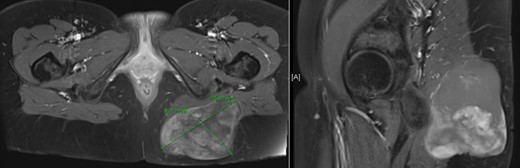

A woman 36 years of age presented with a painless, slowly growing mass of the left buttock (Fig. 1). Magnetic resonance showed an inhomogeneous tumor of 10 × 8.5 × 6 cm3 in size suspicious for myxoid sarcoma (Fig. 2). Biopsy was recommended. However, the patient refused and was lost for follow-up. Three an a half years later, the anemic patient was referred again, now with a giant 22 × 19 × 24 cm3 measuring, foul, ulcerating and bleeding tumor (Fig. 3), partly infiltrating the gluteus maximus muscle (Fig 4). Myxoid sarcoma was confirmed by three deep punch biopsies in local anesthesia followed by swift surgical resection.

Magnetic resonance imaging described a left gluteal tumor, partly situated within the left gluteus maximus muscle, without infiltrating the skin.

Magnetic resonance imaging showed a very large tumor of the left gluteal region, further infiltrating the left gluteus muscle and now with infiltration of the skin.